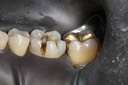

Gary Umeda #18, 19, 20 try in

Gary Umeda #18, 19, 20 finish